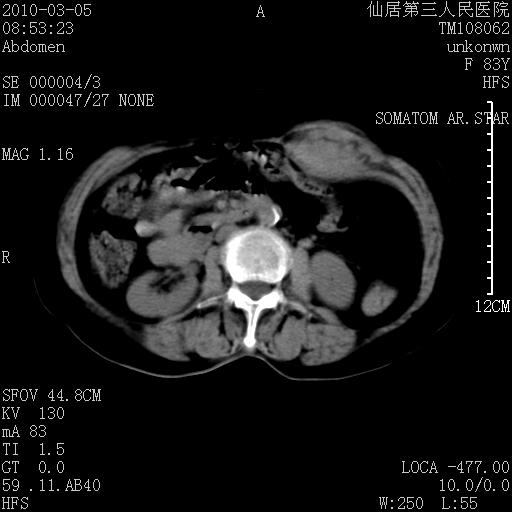

标题: CT24879:腹直肌病变。在线等。

女性,83y,腹痛一周。

考虑:左侧腹直肌神经纤维瘤可能

神经纤维瘤—伴有出血?

有无外伤,血肿或韧带样瘤

考虑左侧腹直肌血肿,肿瘤性病变待排。

增强看看,mfh可能性大,次之可考虑血肿、bfh、转移瘤、神经纤维瘤、侵袭性韧带样纤维瘤等。肝内钙化灶,右肾结石。

支持腹壁纤维肉瘤

血肿,纤维瘤,子宫内膜异位都有可能。